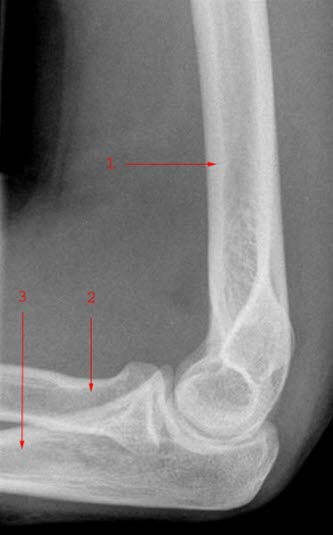

Underarmen består av to bein: spolebeinet (radius) på tommelsiden og albuebeinet (ulna) på lillefingersiden. Disse to beina danner ledd med overarmsbeinet i albuen og med håndrotsbeina i håndleddet. Beina holdes fast sammen av bindevev. Se røntgenbilder av et normalt albueledd sett forfra og fra siden:

Brudd i øvre del av radius, ved overgangen til radiushodet (som danner ledd med overarmsbeinet), og utgjør 5-10% av alle bruddtyper hos barn.